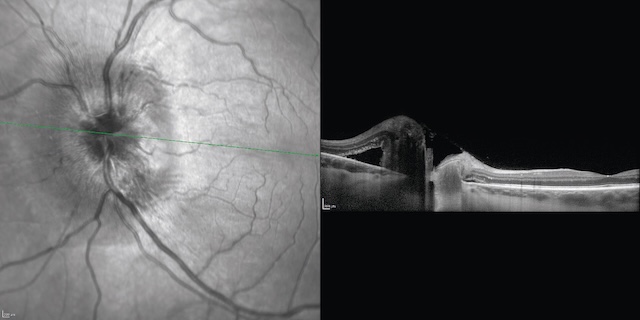

- • œdème papillaire bilatéral (fig. 8.22 et fig. 8.23).

Fig. 8.23 Photographie du fond d’œil gauche et coupe en OCT du même patient qu’en figure 8.22.

L’œdème papillaire est mieux visible en cliché infrarouge, et il existe une surélévation en OCT (coupe passant par la papille).Montage en deux volets illustrant à gauche une photographie du fond d’œil gauche en infrarouge structurel, et à droite une coupe en tomographie en cohérence optique (OCT) horizontale passant par la macula. L’image en fond d’œil montre un nerf optique au contour flou, avec une hyperréflectivité maculaire évoquant une traction vitréomaculée ou une membrane épirétinienne. Sur la coupe OCT correspondante, on observe une distorsion nette du relief fovéal, avec soulèvement de la rétine centrale et désorganisation architecturale des couches internes. Une traction antéro-postérieure visible entraîne une cavitation sous-fovéolaire et un soulèvement rétinien focalisé. Ce type de présentation évoque une traction vitréomaculaire symptomatique, nécessitant un suivi spécialisé, voire une intervention chirurgicale.